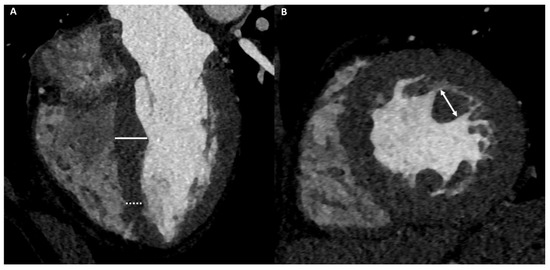

4.2.5. Cardiac Imaging: AH vs. Infiltrative Cardiomyopathy

- Ramirez, R.; Trivieri, M.; Fayad, Z.A.; Ahmadi, A.; Narula, J.; Argulian, E. Advanced Imaging in Cardiac Sarcoidosis. J. Nucl. Med. 2019, 60, 892–898. [Google Scholar] [CrossRef] [PubMed]

| LGE/LIE | |||||||

| Type | Linear | Patchy or massive | Linear | Linear | Linear | Linear | Linear or parchy |

| Layer | Mesocardial | Mesocardial | Mesocardial | Mesocardial | Subepicardial Mesocardial | Subepicardial | Subendocardial Mesocardial |

| Site | Interventricular juctions | Hypertrophic area; interventricular junctions | Septum; infero-lateral LV wall | Variable, not associated with NC area | Anterior RV wall | Infero-lateral LV wall | Circumferential; septum; lateral LV wall |